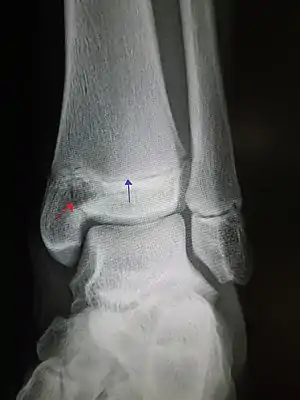

![]() | |

| An X-ray of the left ankle showing a Salter–Harris type III fracture of medial malleolus. Black arrow demonstrates fracture line while the white arrow marks the growth plate. | |